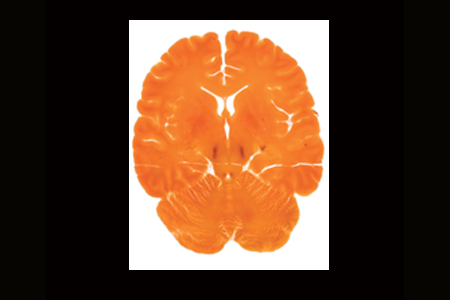

描述:冠狀切片